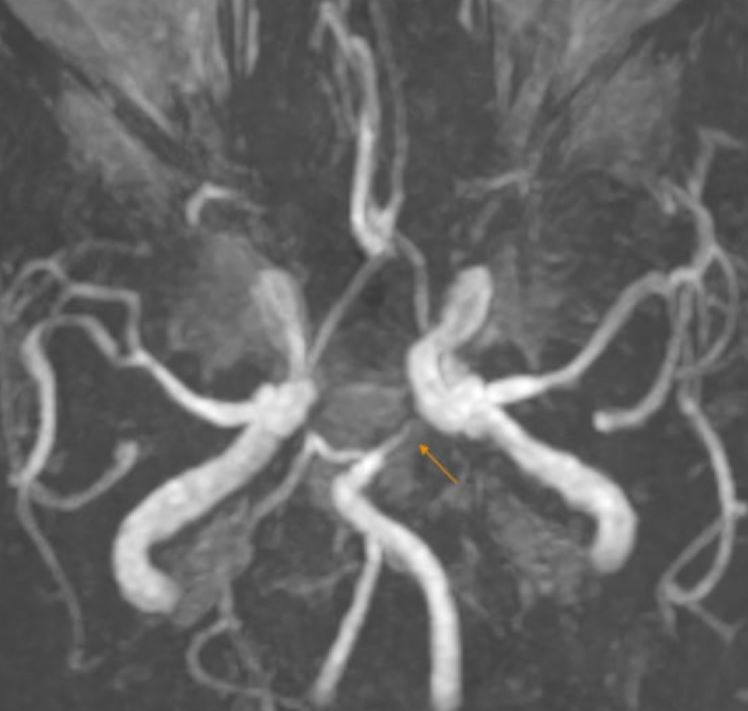

Kết quả xét nghiệm cho thấy chỉ số đường máu, mỡ máu tăng cao. Quá trình siêu âm mạch cảnh, bác sĩ phát hiện hình ảnh xơ vữa động mạch gây hẹp nhẹ - vừa lòng mạch. Chụp MRI sọ não thấy hình ảnh nhồi máu não cấp vùng chẩm trái, kèm thoái hóa myelin chất trắng dưới vỏ và quanh não thất bên hai bên.

Kết quả chụp MRI sọ não phát hiện nhồi máu não cấp vùng chẩm trái

Dựa vào các kết quả lâm sàng và cận lâm sàng đã thực hiện, bệnh nhân được chẩn đoán xác định một loạt bệnh lý nguy hiểm gồm nhồi máu não cấp vùng chẩm trái, tăng huyết áp, rối loạn chuyển hóa lipid máu.